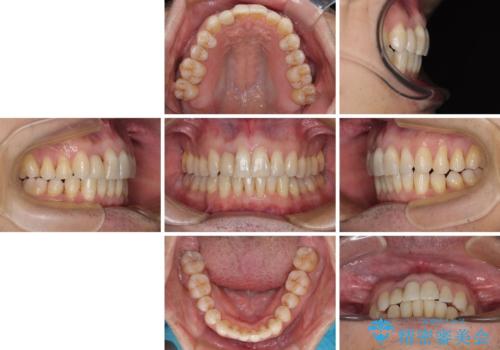

前歯のクラウンは変色が著しいため、矯正治療後にオールセラミッククラウンにて補綴治療を行うこととしました。

担当医としてはもう少し前歯のデコボコを改善したいところでしたが、患者様としては十分に満足いく歯列であり、マウスピース矯正に飽きてしまったとのことで、治療終了となりました。